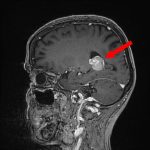

624

'25年4月

70代

後頭葉膠芽腫

頭蓋内腫瘍摘出術

No.’25_26 手術前1

No.’25_26 手術前2

No.’25_26 摘出 前

No.’25_26  摘出 中

No.’25_26 摘出 後